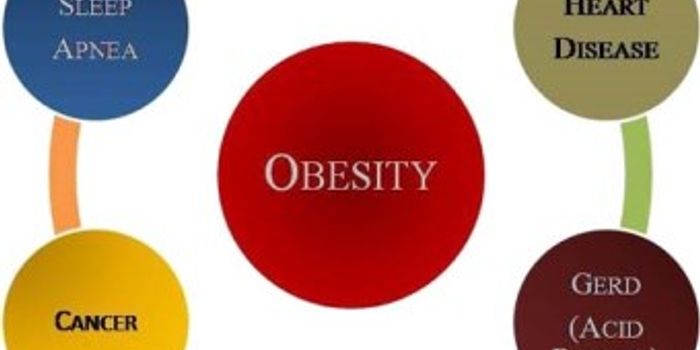

MAY 24, 2015Health & MedicineObesity has long been a global epidemic with an estimated 2.8 million people dying each year from associated complicatio ...

JAN 25, 2022CancerObesity is related to various types of cancer. Numerous epidemiological studies have demonstrated that the risk of ...